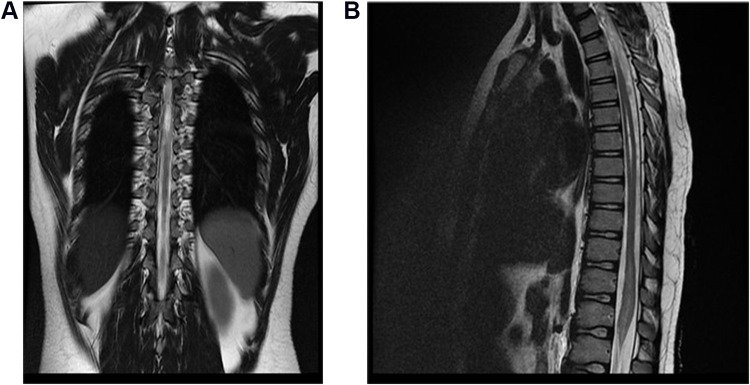

Case presentation: The case of acute transverse myelitis in a 12-year-old child corresponds to the existing definition of a vaccine-associated paralytic poliomyelitis case: a temporal relationship between the onset of flaccid paralysis and the administration of oral polio vaccine and the duration of paralysis. The child developed flaccid paralysis 18 days after (August, 2024) the administration of oral polio vaccine and persisted for more than 60 days from the onset of the disease. Vaccine virus type 3 was isolated from the feces. However, the child received 2 doses of inactivated oral polio vaccine and 1 dose of bivalent (types 1 and 3) oral polio vaccine before the disease. The child did not have an increase in the titer of antibodies in paired sera to polioviruses types 1 and 3. Spinal cord magnetic resonance imaging revealed an intramedullary focus with hyperintense MR signal on 2WI, 2FS at the level of the spinal cord cone (Th11-L2), which spread across the entire diameter and unevenly accumulated paramagnetic. These changes were characteristic of acute transverse myelitis.